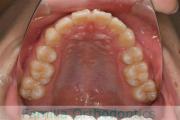

No.22V-449

- 主な症状:

- 上顎前突

- その他の症状:

- 叢生

- 年齢:

- 14歳

- 性別:

- 男性

- 抜歯部位

- 上:

- 44

- 下:

- 8448

- 主な使用装置:

- FEA

- 治療にかかった費用:

- 87万円

歯並びをきれいにしたいということで来院されました。上下左右から小臼歯を抜歯して、マルチブラケット法を行っています。2年弱、25回程度の通院が必要でした。

かなり強い叢生(でこぼこ、凹凸、ガタガタ)ですので、保定をしっかりしないと後戻りのリスクがあります。

- ≫治療前

-

上顎